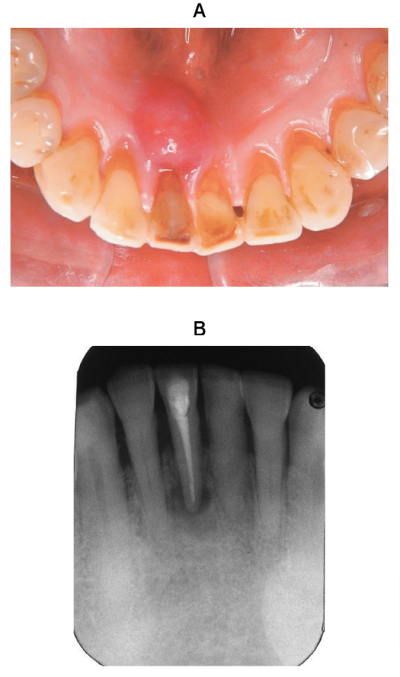

60 歳の男性。下顎右側中切歯部の歯肉腫脹を主訴として来院した。2年前に1⏋の根管治療を受けたが、2日前に腫脹に気付いたという。現在、痛みはない。腫脹部に波動を触れる。初診時の口腔内写真とエックス線画像を別に示す。

診断に有用なのはどれか。1つ選べ。